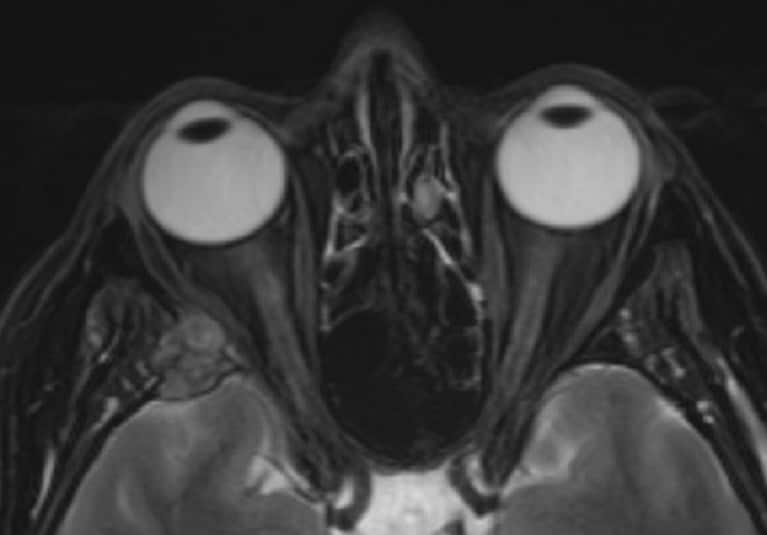

Dual focus, one goal: Neuro-ophthalmology provides comprehensive evaluation for an accurate diagnosis

Mayo Clinic offers specialized care in neuro-ophthalmology, which includes treating a broad spectrum of diseases such as defects of the neuromuscular junction, cranial neuropathies or inflammation of the optic nerves.